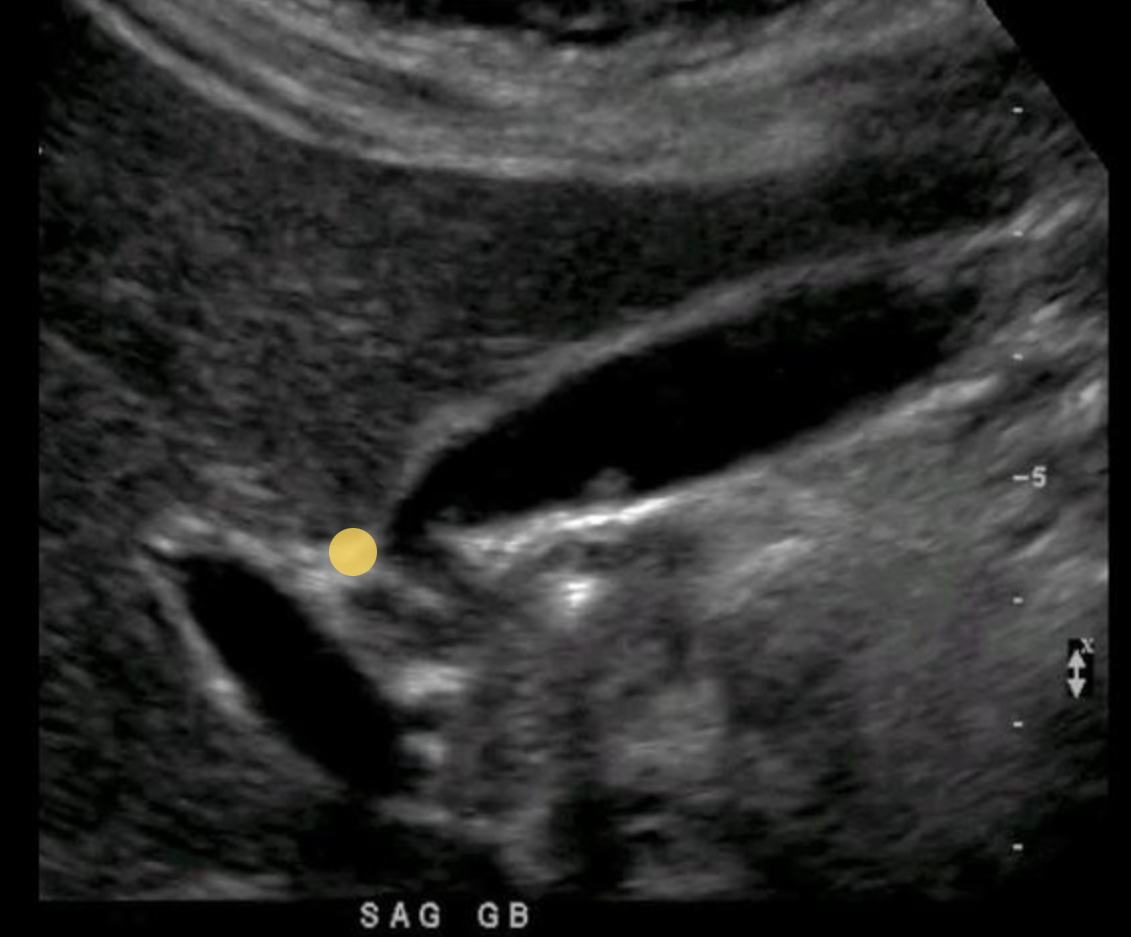

What structure is indicated by the purple circle?

Portal triad